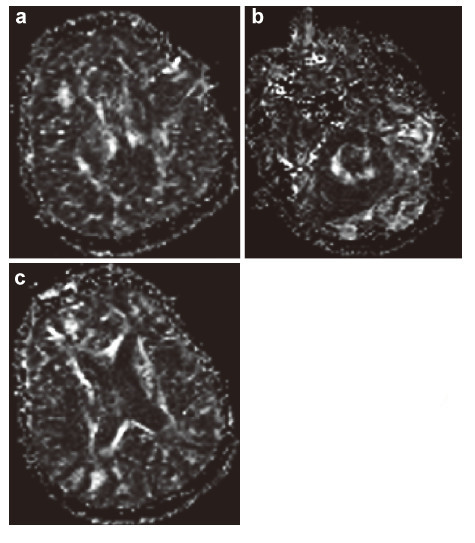

The obtained multi‐level data about the condition of the patient’s brain must be provided at contemporary carriers (CD,DVDs,flash drives,etc.) for the bioinformation analysis and they must be recorded in DICOM standard. The requirements for the research at this stage are the following: (1) No less than 1.5 Tesla MRI. (2) MRI tractography of conduction pathways in the site of injury of the brain/spinal cord. (3) MRI angiography of the brain vessels. (4) PET of the brain or a whole body,for spinal cords the standard radioisotopes of glucose PET must be done. (5) No less than 32 slice spiral CT of the brain or the spinal cord and spine. (6) Cerebral EEG mapping must be on the EEG equipment with the software for 3D local modeling of the bioelectrical activity of the brain/spinal cord. (7) MEG of the brain with 3D modeling.

The time period between different imaging tests should be not more than a week. All imaging tests that were done at the preparatory stage for the examination can be used at the next stage to monitor the effectiveness of the therapy. The imaging data can be fused into 3D maps of the brain with the help of the Multimodal fusion 3D software of the Cyberknife robotic radiosurgery system or similar systems for stereotaxic radiotherapy of other manufacturers. With this approach a three‐dimensional multi‐level mapped model of the information structure of the damaged NT of the brain/spinal cord of the nerve or mental disease case can be represented as the set of the tables of local data,that correlate them with anatomical formations in the brain so that the personalized functional 3D map of pathological changes and damages the NT of the specific case. Such a 3D map can be the basis for the marking and stereotaxic targeted therapeutic radio‐bioengineering effect of IR on the brain or spinal cord. This stage of the proposed treatment of nervous and mental diseases can be illustrated by the clinical case of the patient B. Figures 2-7 represent the data of different stages of the technology of multilevel fusion of the data of computerized tests.

|